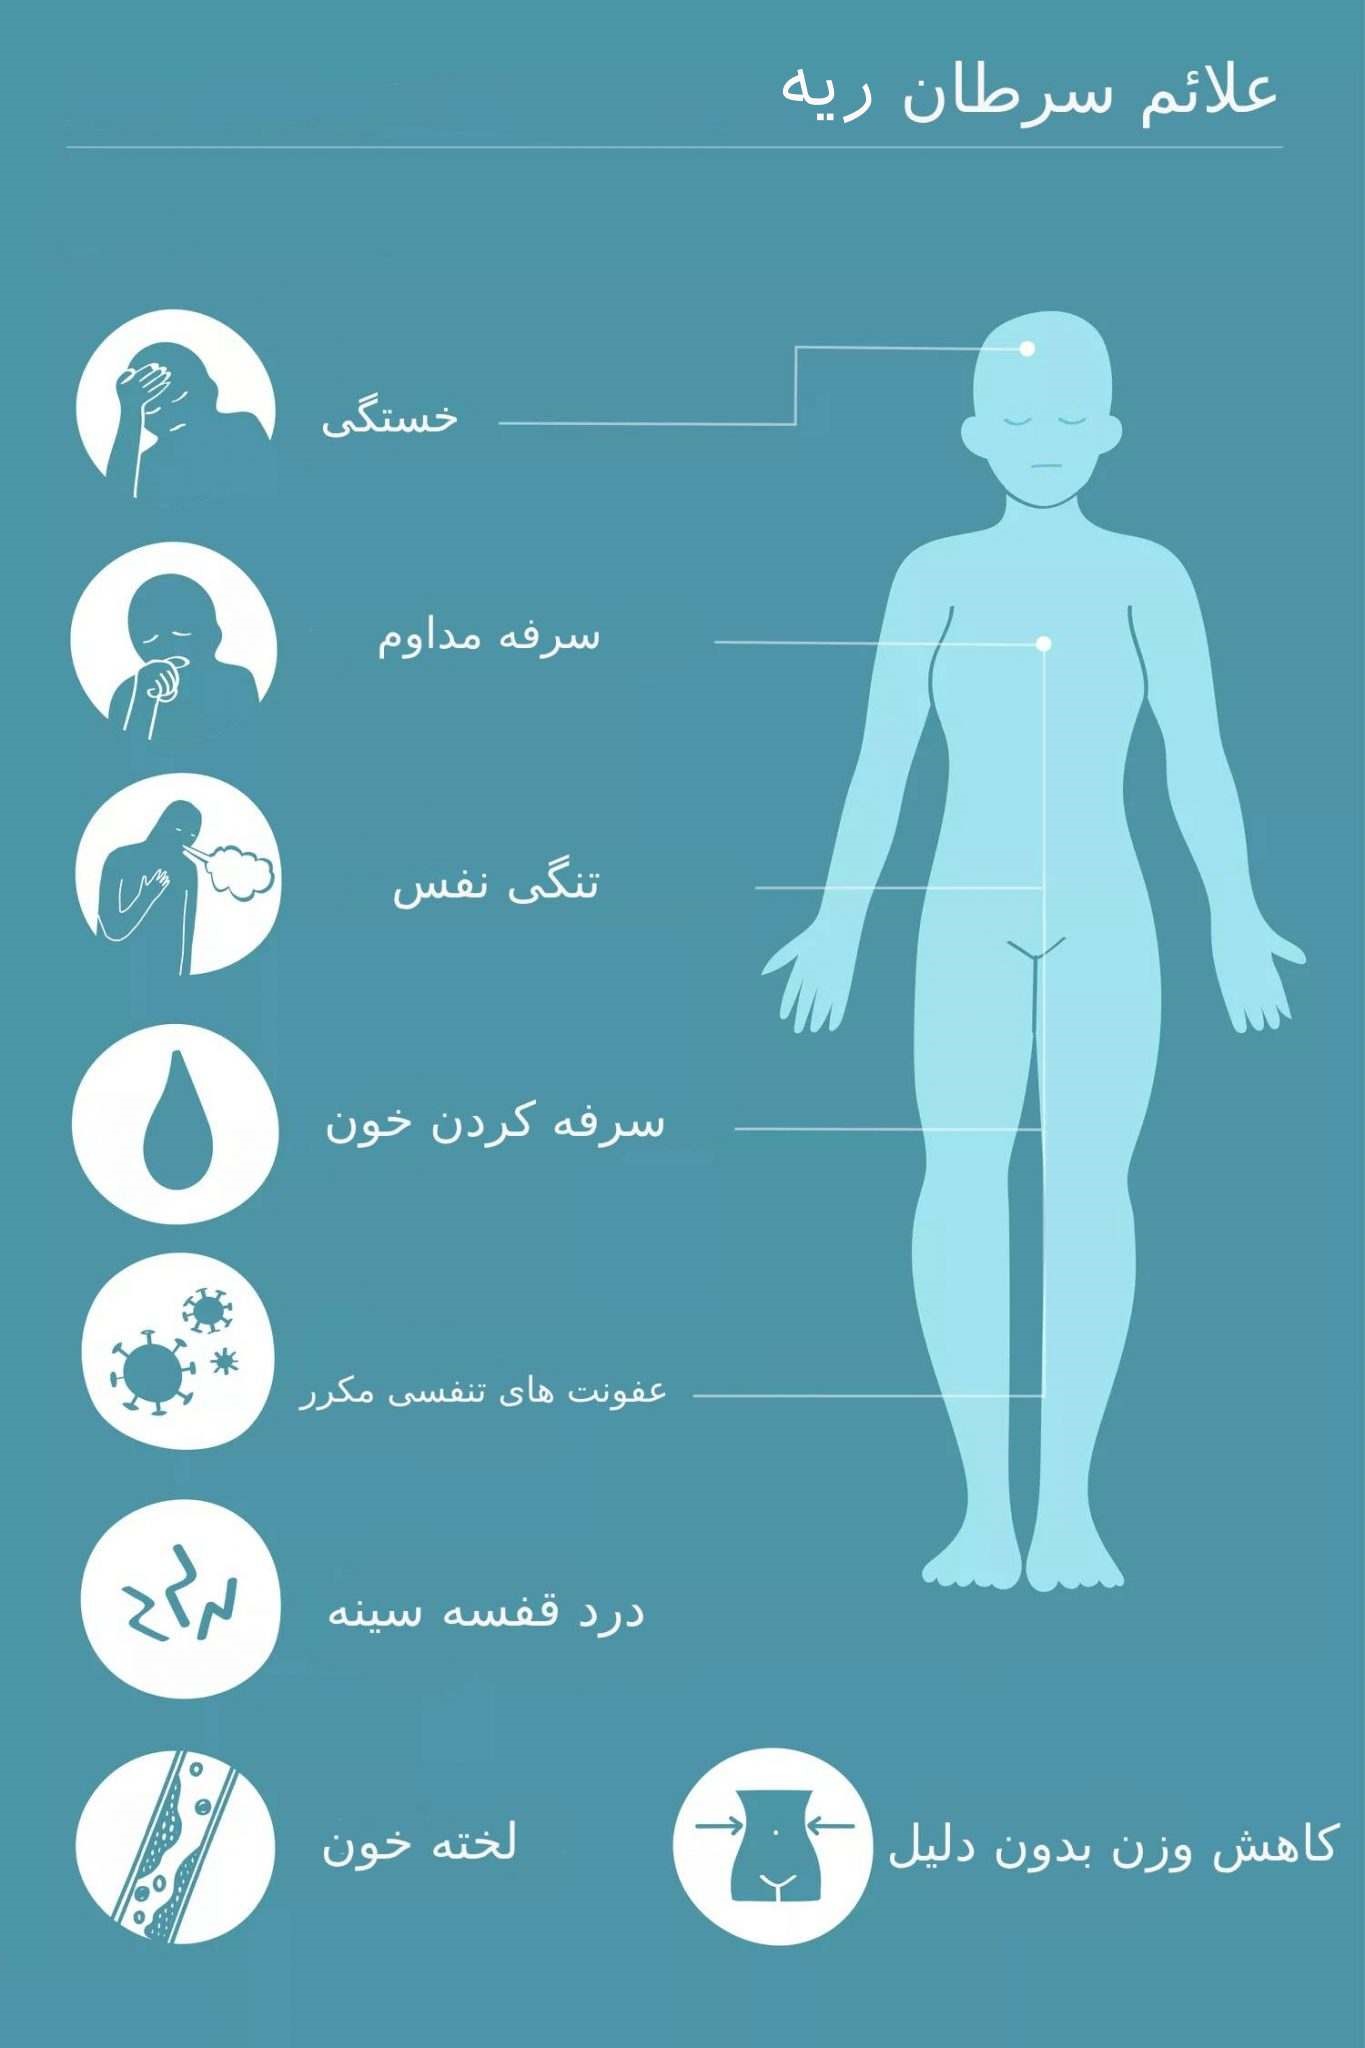

علائم سرطان ریه

علائم سرطان ریه ممکن است در مراحل اولیه ظاهر نشوند، اما با پیشرفت بیماری میتوانند شامل سرفه (گاهی با خلط خونی)، کاهش وزن، تنگی نفس، درد قفسه سینه، تب و تعریق شبانه باشند.